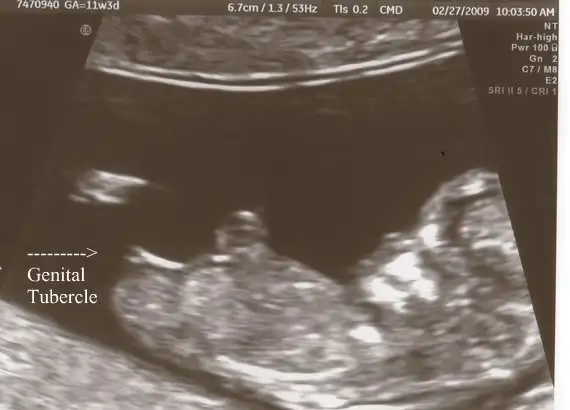

Eki Görüntüle 558235 11+3

Bunlarda internetten bulduğum kız olması beklenirken erkek doğan bebeklerin usgleri![]()